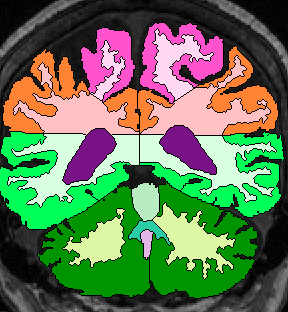

| Parietal Lobe White Matter: Extend fronto-parietal gray matter boundary more or less straight to the CSF Third vents (fig 8). When third vent is gone, simply extend fronto-parietal boundary line to intersect with temporo-parietal boundary. Extract this parietal white matter area, but leave unlabeled for the time being.

When parietal gray matter shows up medially, extend the boundry lines to intersect. Continue to do this when occipital lobe appears (fig 7). At this point, most of the boundaries are already drawn.

Finally, label all unlabeled extraction as Parietal Lobe White Matter. |